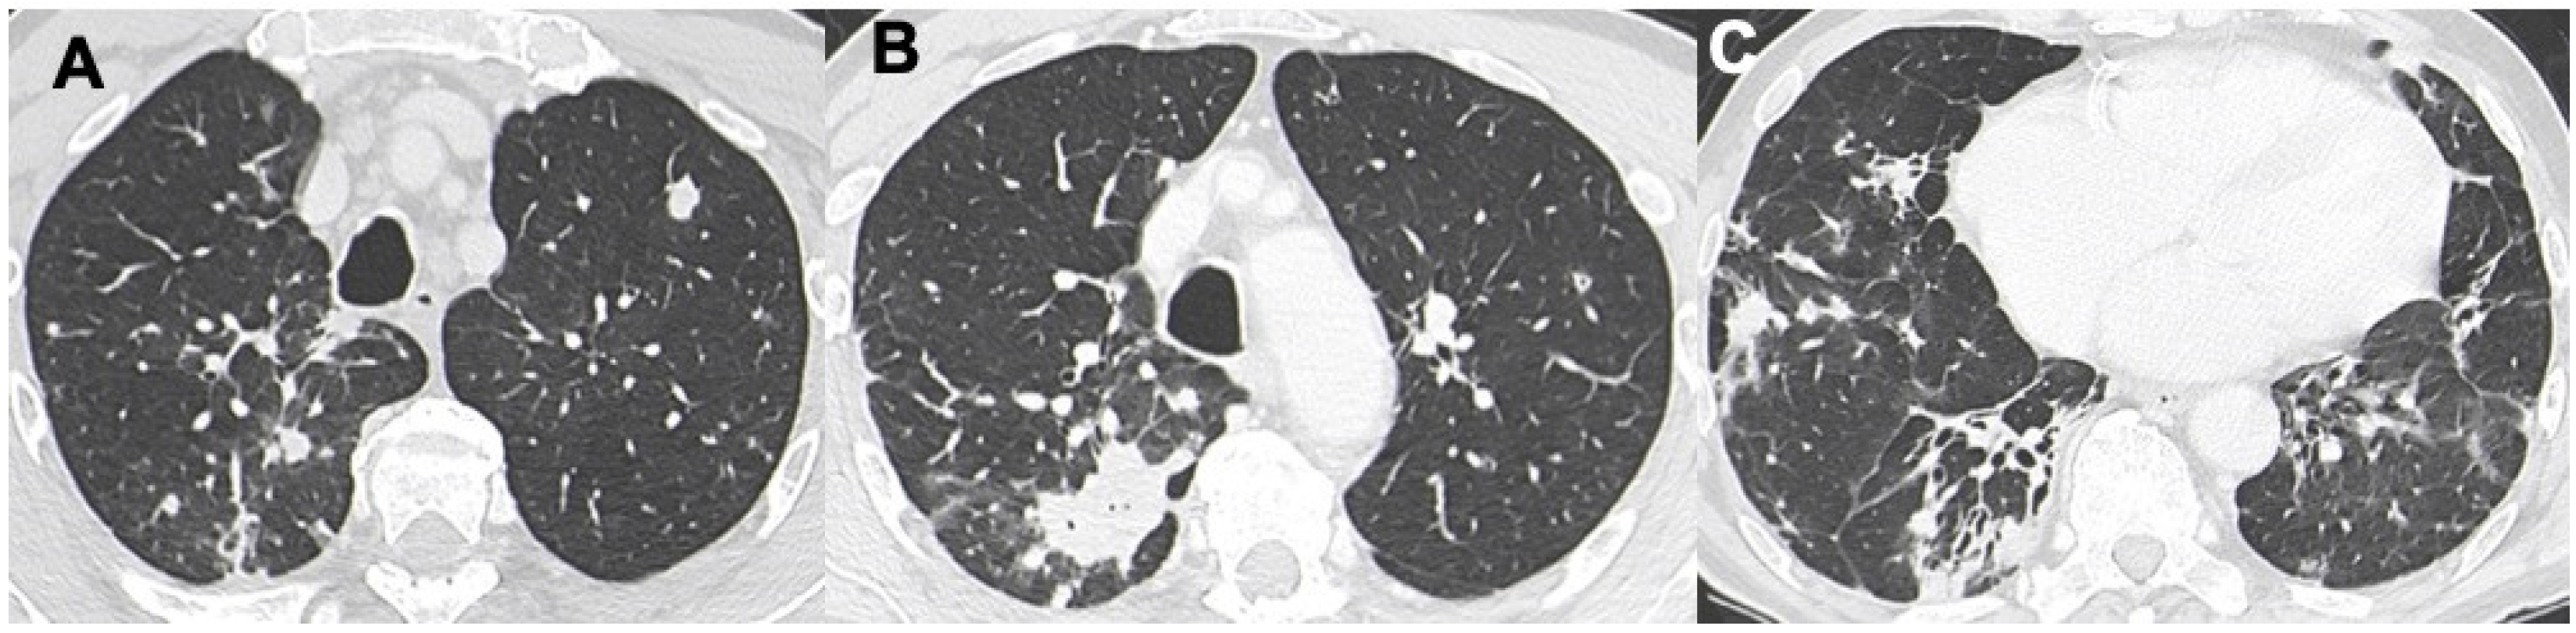

3.2. Nodules and Masses

3.3. Ground-Glass Opacities

| DLBCL | Masses and nodules, mediastinal nodes enlargement, GGO | Neoplasms, LYG, metastasis |

| LIP | Air-filled cysts, “halo sign”, masses and nodules with centrilobular appearance, GGO, patchy interstitial involvement | Infections, metastasis, neoplasm, MALT, sarcoidosis, amiloidosis |

| LYG | Masses and nodules with peribronchovascolar distribution, basal predominance, GGO, “halo sign”, “reverse halo sign” | Vasculitis, sarcoidosis, neoplasms, metastasis, PTLD, angioinvasive aspergillosi, DLBCL |